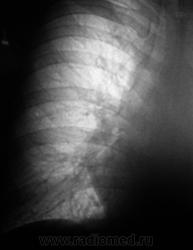

Боковая проекция.